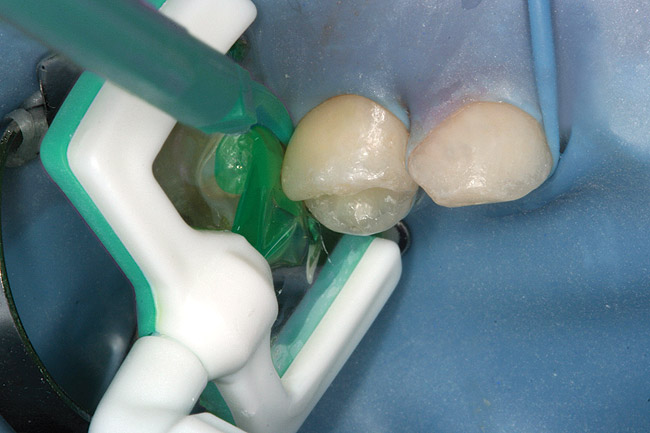

Specially designed dental wedges are inserted to slightly separate the carious tooth from adjacent teeth. A 15% hydrochloric gel is used to remove the "pseudointact" surface and open the pore system of the incipient lesion body (Figure 7).85 After rinsing (Figure 8), the area is dried with ethanol (Figure 9), followed by dry air. Then, the infiltrant is applied and allowed to penetrate the lesion pores by capillary action for 3 minutes (Figure 10). Any excess material is removed with dental floss, and the infiltrant is light cured from three angles for 40 seconds (Figure 11). A second layer of infiltrant is applied for 1 minute, and light cured for 40 seconds (Figure 12).86 It should be noted that the infiltrant is not radiopaque because fillers would affect the viscosity. Efficacy of the treatment can be tracked at future visits by lack of lesion progression.

Figure 10  Icon Infiltrant flowing through matrix channel into contact area on mesial of tooth A.

Figure 10